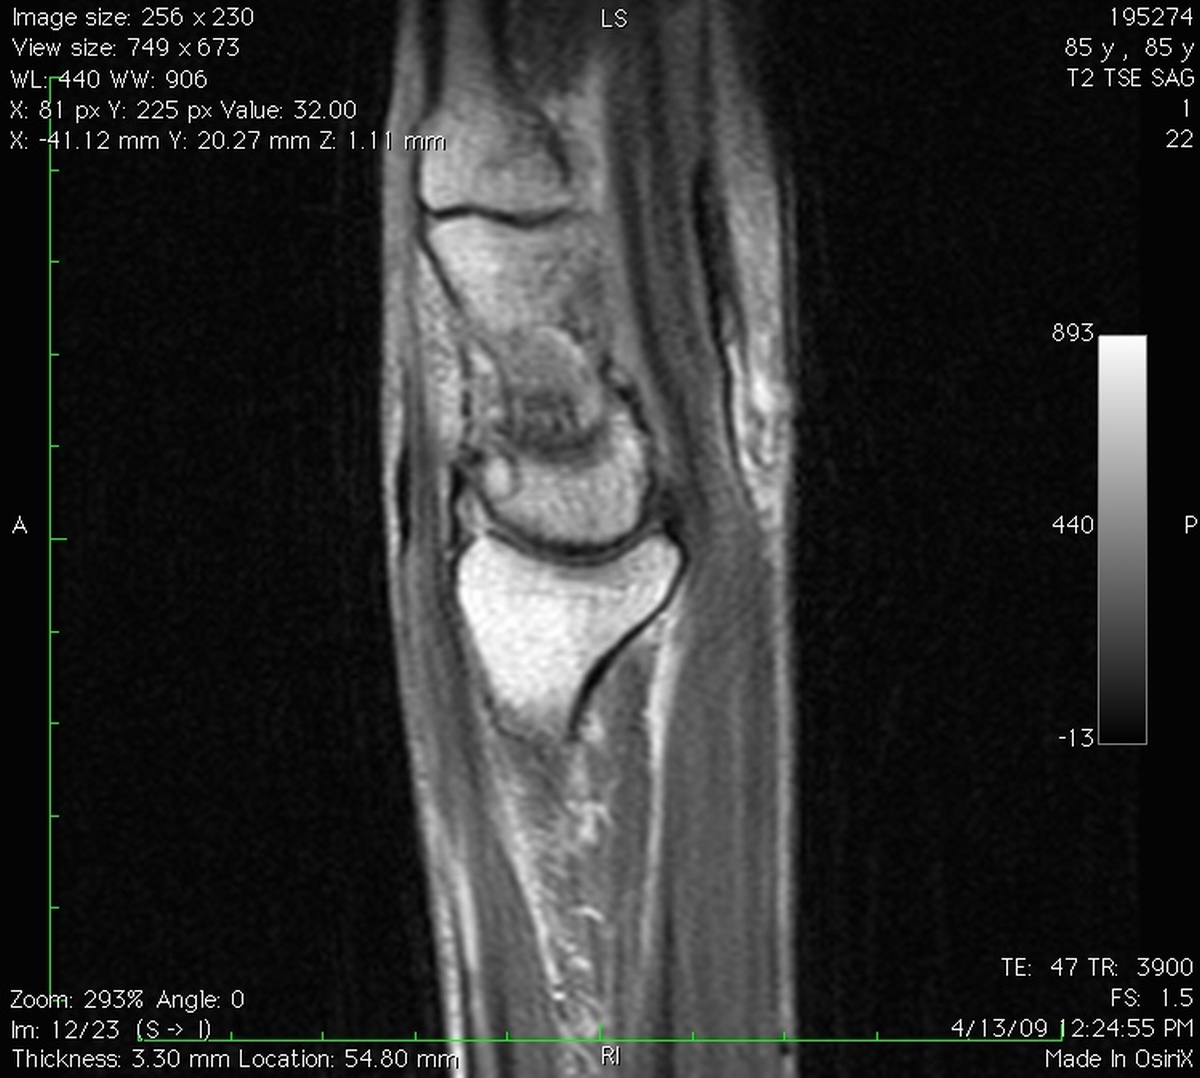

Clinical Example: Lunate Cyst

This imaging series was obtained for evaluation of a one month history of painful pronosupination in an active 85 year old man whose daily exercises include pushups.

lunate cyst